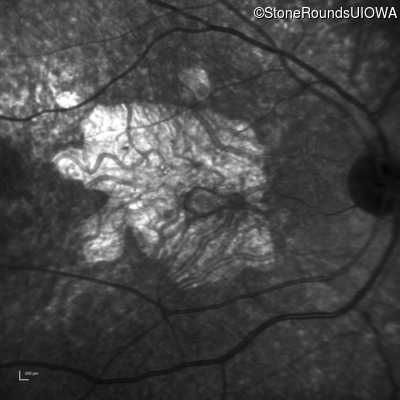

This 30 year old man first noticed poor vision in dim light when he was five years old. His visual acuity began to fall in his early 20's.

Diagnosis & molecular findings

Disease Gene Allele 1 variant(s) Allele 2 variant(s) Inheritance mode

Macular Disease WDR19 His344Arg CAT>CGT Ser485Ile AGT>ATT AR